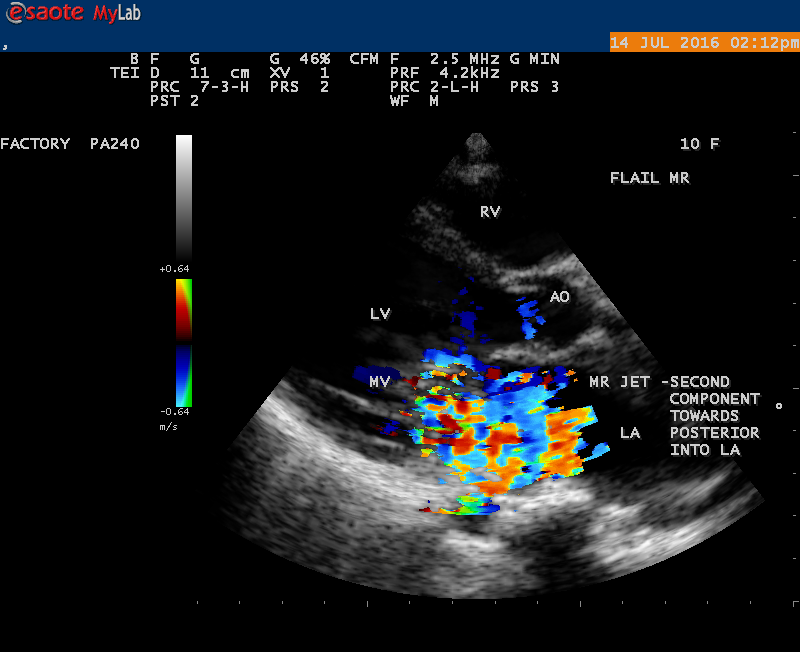

A 10 year female child was referred for echocardiographic evaluation with an apical systolic murmur. The child was having recurrent episodes of rheumatic fever (febrile illness with joint pains) at the age of 5-6 years and taken some treatment from the local medical practitioner, but she was not taken penicillin prophylaxis earlier. The child was remained afebrile for long period and no precipitating factors of infective endocarditis such as dental or genitourinary procedures in the past. General examination revealed normal growth and development, no cyanosis and clubbing and peripheral signs of infective endocarditis such s Osler’s nodes, Janeway lesions, Roths spots and splinter haemorrhages are not present and they are relatively rare in children. Physical examination revealed a grade 3/6 , blowing, high pitched, holosystolic murmur with a constant intensity and duration on dynamic auscultation and loudest at the apex with a radiation to left axilla and transmitted to the left infrascapular area and vertebral coloumn and it is due to the flow generating the murmur is directed posterolaterally within the left atrial cavity, suggesting the murmur of mitral regurgitation due to the rupture of chordae tendineae of anterior mitral leaflet. Blood culture revealed normal. Blood chemistry revealed the positive serum ASO titer, suggesting a recent streptococcal infection and other parameters are normal. X- ray chest reveled moderate cardiomegaly and ECG revealed a left ventricular volume overload pattern of eccentric hypertrophy due to LV dilatation as a result of severe mitral regurgitation and a normal rhythm. Transthoracic echocardiography revealed a giant vegetation ‘popcorn’ like in Figures 1,3 and 4 and ‘cucumber’ like in Figure 2, mainly attached to base and apical portion of anterior mitral leaflet as shown in Figure 31 and manifested in various size and shapes as shown in Figures 1 to 33. A flail anterior leaflet with a disorganized mitral regurgitation jet as shown in Figure 16 and 21 and the posterior leaflet is embedded with vegetation and resulting in ‘kissing forms’ as shown in Figures 13, 14 and 15 in echocardiography imaging. Tricuspid valve is also thickened and calcified as shown in Figure 2 in addition to thickened and calcified mitral leaflets, suggesting an underlying rheumatic etiology predisposing to the formation of vegetation. The child was given 1.2 million units of intramuscular benzathine penicillin injection as a therapeutic and initial prophylaxis dose for rheumatic fever and advised every 3 weeks for life long. Small doses of digoxin and diuretics are also prescribed and advised early surgery (mitral valve replacement) Transthoracic 2D images are as in Figures 1 to 33 are given below

The most common and direct evidence of infective endocarditis is the vegetation and it begins as a microscopic focus of infection and gradually grows into a conspicuous mass. It is typically an irregularly shaped, highly mobile, echogenic mass attached to the free edge of a valve leaflet ( most commonly at the coaptation line) and tends to develop on the ‘upstream’ side of the valve leaflets ( ie, the ventricular side of aortic valve and the atrial side of mitral and tricuspid valves. They may be seesile or pedunculated, but usually has an oscillating or fluttering motion, a typical feature of most vegetations. Vegetation move with the leaflet in a more chaotic (‘oscillating’) manner and it may prolapse through the valve into the LV (left ventricle) as it opens as shown in Figures 3, 4 and 16 and into LA (left atrium) as it closing (Figure 5 and 6) . The mass of vegetation is typically homogeneous with echogenicity similar to that of the myocardium. The infectious process often alter the valvular structure and function. Extensive involvement of the leaflet may result in chordal rupture, leading to severe regurgitation as shown in Figure 21 . Direct and typical signs of RMCT (ruptured mitral chordate tendineae) were chain-flail or whiplash-like changes and had an incidence of 86.7%, causing severe regurgitation and mitral chordal rupture is the leading cause of flail mitral leaflet[30]. A large vegetation may obstruct the valve orifice as shown in Figure 1 and 2 , sometimes termed as “obstructive-type bacterial endocarditis” and producing a functional valve stenosis ( Ping-Pong mitral stenosis [31]) similar to left atrial myxoma as shown in Figure 29.

The size and shape of vegetation vary due to curling of vegetation. The size of vegetation in this child is 35.6 x 9.3 mm as in Figure 17 , 20 x 23.7 mm as in Figure 1 , 32.9 x 13.9 mm as in Figure 2 .

The shape of vegetation varies in this child as ‘popcorn’ like (Figures 1,3 and 4 ), rod-shaped (Figure ), basket shaped (Figure 7 )[33-Figure 13.3], ‘baby in hand’ appearance (Figure 18), ‘cucumber shaped (Figure 2 ) and a ‘bunch of plantain’appearance (Figure 33 ), ring shaped (Figure 19 }, bileaflet structure (Figure 9 )with bileaflet MR jet as shown in Figure 10 . and kissing forms (Figure 13 - parasternal long axis view, Figure 14 - apical four chamber view and Figure 15 - short axis view)

The anatomic disruption of a portion of the mitral valve apparatus dueto the underlying rheumatic valvulitis with predisposing infective endocarditis which form a vegetation , resulting an eccentric regurgitation jet with orientation opposite in direction of the leaflet having the anatomic defect such as ‘flail’. In the presence of ‘flail leaflet’, the mitral regurgitant spectral signal may have an atypical appearance and the flail portion oscillate in the spectral signal of regurgitant flow stream to produce a ‘tiger stripe’ appearance as shown in Figure 27. associated with ‘whistling’ sound on auscultation[33-Figure 11.85]. The mitral regurgitation (flail MR) jet is chaotic as shown in Figure 26, highly eccentric (Figure 22) and disorganized with one component behind the anterior mitral leaflet and the second component directed towards posterior immediately as in Figure 21 [33- Figure 11.79].